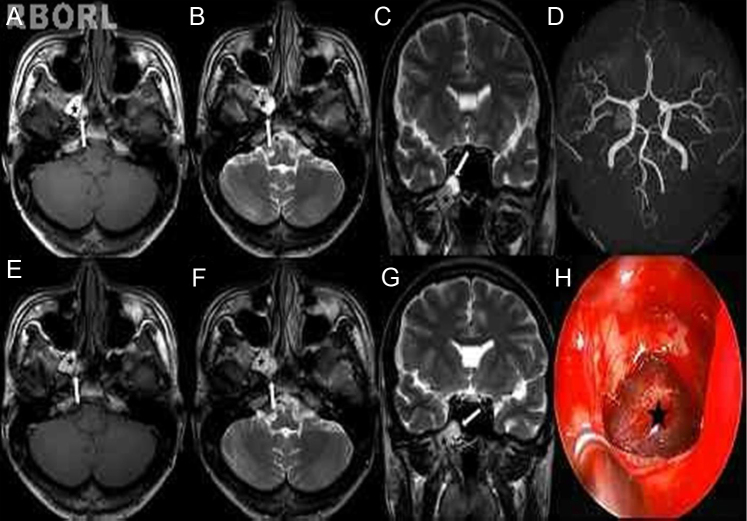

A 23-year-old, previously healthy male presented with right-sided headache over six months. The headache was intermittent and dull, but recently it had become more severe in intensity. The neurological examination was normal. In order to exclude other symptomatic headaches, brain magnetic resonance imaging (MRI) was performed by his neurologist, which showed no intracerebral structural lesions. However, it revealed a cystic lesion in the right sphenoid sinus, without erosion of the bony wall (Fig. 1). Since his neurologist thought this lesion was not associated with the headache, it was decided to observe changes in size for six months. Although non-steroidal anti-inflammatory drugs (NSAIDs) had some effect, his headache was not completely relieved, and recently became more aggravated. Six months later, brain MRI was re-evaluated because of his ongoing and aggravated headache; it showed no change in size, but minimal changes in signal intensity (Fig. 1). The provisional diagnosis attributed the headache to the right sphenoid sinus mucocele. After the right-sided sphenoidotomy, a brownish cystic mass was found and excised completely (Fig. 1). The patient has been completely relieved of his symptoms for the last 12 months.

Figure 1.

(A–D) The muocele is composed of two separate parts. T1-weighted magnetic resonance imaging (MRI) scan (A, axial) shows a hyperintense part (black star: high protein content) and a mildly hyperintense part (white arrow: high water content). T2-weighted MRI scans (B, axial; C, coronal) shows a hypointense part centrally, with a surrounding rim of hyperintense mucosa (black star) and a part of a high signal. MRA scan (D) shows normal arterial vasculature and a mucocele. (E–G) Six months later, brain MRI was re-evaluated. It showed no changes in size, but minimal changes in signal intensity of the lesion. The T2-weighted signal is lower than expected in the part of high water content (white arrow), indicating the increase of protein within the mucocele. (H) After wide sphenoidotomy, the blackish cystic mass (black star) was found and completely removed by endoscopic surgery.

Mucoceles may have variable signal intensities on MRI depending on their protein content, inspissation, and possible superinfection.2 In the present patient, there was a hyperintense lesion on T1-weighted MRI, which showed lower than expected enhancement on T2-weighted MRI, consistent with high protein contents.2, 6 On follow-up MRI, there were some changes in signal intensity, suggesting an increase of protein content within the mucocele associated with increase of inflammatory cytokines.